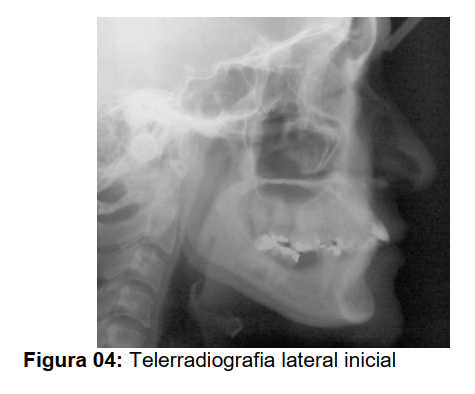

A paciente N. A. B. S., 30 anos, gênero feminino, procurou tratamento ortodôntico para intrusão do segmento posterior superior direito e esquerdo, que se encontravam-se extruídos devido à perda precoce dos elementos posteriores inferiores direito e esquerdo (Figura 1). Ao exame clínico constatouse que a mesma apresentava perfil reto com selamento labial passivo, sendo o tipo facial da paciente braquicefálico. Na análise de face a paciente apresentava o formato oval.

Nas telerradiografias inicial e final, foi construído o ponto centróide na coroa dos primeiros molares que sofreram intrusão com mini-implante. Uma linha vertical foi traçada perpendicularmente ao plano palatino unindo o mesmo ao ponto centróide (Figura 10). Desta forma pode-se medir a quantidade de intrusão dos primeiros molares superiores sendo que o dente 16 intruiu 3mm e o 26 intruiu 3,5 mm.

Para avaliação de possíveis angulações dentárias, traçou-se uma linha passando pelo longo eixo do primeiro molar superior (LEM6S) formando um ângulo com a linha SN. O valor deste ângulo, medido nas telerradiografias inicial e final, permitiu identificar se o primeiro molar superior sofreu angulação durante a mecânica de intrusão (Figura 10). Neste trabalho a alteração com relação ao valor de inclinações dos molares foi insignificante demonstrando uma intrusão real destes dentes.